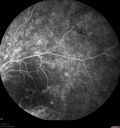

FLUORESCEIN ANGIOGRAPHY: Fluorescein angiography shows hyperfluorescence in a pattern consistent with retinitis pigmentosa variance, where there is sparing of the central macula with increased hyperfluorescence in the periphery.